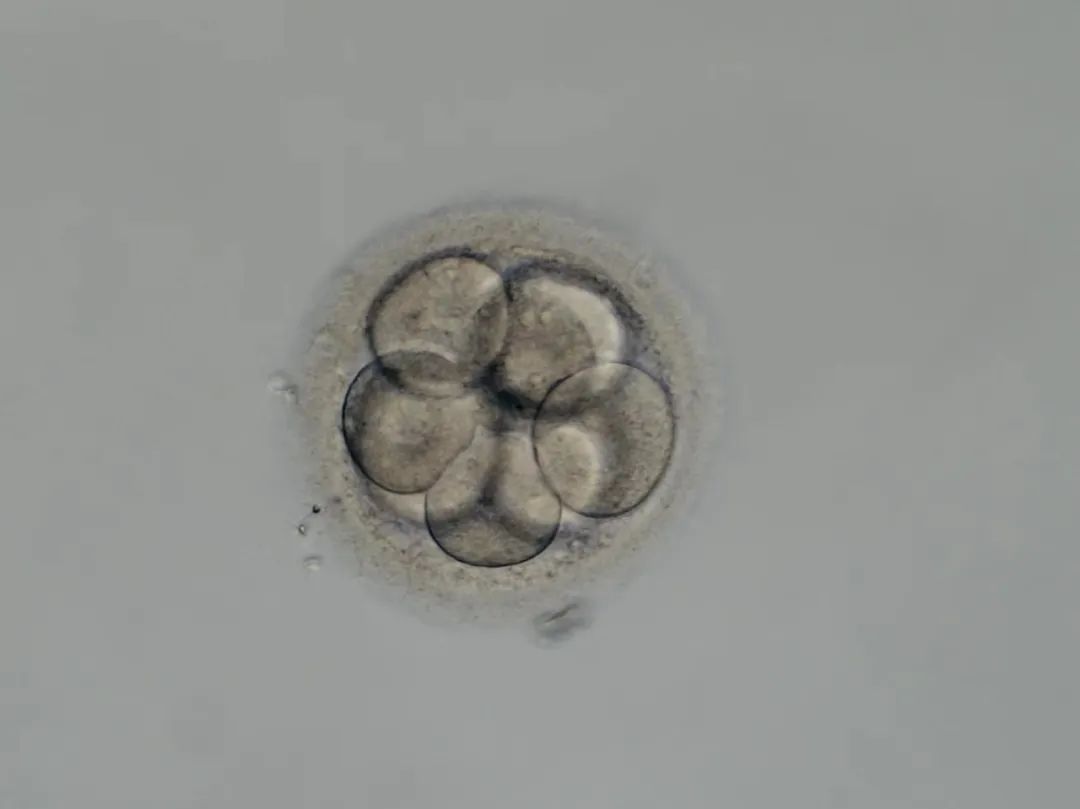

2022年12月,长春市一对高龄夫妇(女42岁,男46岁)在该院生殖医学中心接受了试管婴儿手术。成功移植后,经过14天的漫长等待,血清学检测结果显示已成功受孕。首例试管婴儿在该院的成功,标志着医院辅助生殖技术实现了新突破,填补了多年来该项技术在该院的空白。

12月25日,两枚优质胚胎顺利移植!14天后,显示成功受孕!